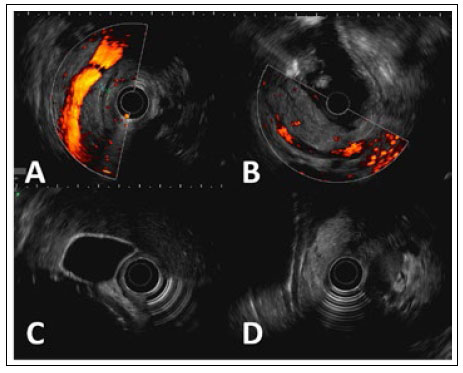

Tras el alta, retornó a Perú, donde se realizó una colangiorresonancia magnética contrastada, que mostró signos de proceso inflamatorio pancreático y peripancreático, derrame pleural laminar bilateral, así como resaltó la ausencia de colelitiasis o barro biliar, el árbol biliar de aspecto conservado, sin dilatación coledociana y ausencia de líquido libre en cavidad abdominal (Figura 2). Inmediatamente se realizó, de forma complementaria, una ecoendoscopía diagnóstica, donde se hallaron signos compatibles de pancreatitis aguda residual en la cola del páncreas, la presencia de un balón intragástrico también destacó que la vesícula y la vía biliares extrahepáticas se mostraron de aspecto conservado, sin presencia de litiasis en todo su trayecto (Figura 3).

Figura 3 Ecoendoscopía radial. A: Cuerpo del páncreas, con presencia de ducto pancreático de calibre conservado y aspecto filiforme.B: Cola del páncreas, con aumento de volumen del parénquima pancreático y presencia de escaso edema peripancreático. C: Vesícula biliar, de paredes delgadas y ausencia de contenido ecogénico en su interior. D: Colédoco de 4,35 mm, visualizado en toda su extensión, sin imágenes litiásicas en su lumen.

En un meta-análisis reciente de 7 estudios que incluyeron 2152 pacientes, el balón intragástrico Elipse demostró ser seguro y efectivo (disminución del IMC, circunferencia de cintura y triglicéridos), así como probó ser tolerable y con un mayor perfil de seguridad en comparación a otros dispositivos similares; dentro de los efectos adversos descritos son el dolor abdominal (37,5%), vómitos (26,9%), diarrea (15,4%) y obstrucción del intestino delgado (0,5%), aunque no se describieron casos de pancreatitis 12. Dentro del resto de modalidades de balón intragástrico, las complicaciones más comunes asociadas son: dolor abdominal, obstrucción del tracto de salida gástrico, náuseas, vómitos recurrentes, erosión esofágica y gástrica, perforación gástrica, neumonía y laringoespasmo. La pancreatitis ha sido descrita inicialmente de manera incidental, aunque ha cobrado mayor protagonismo en la última década probablemente asociado a una mayor masificación de dicho procedimiento endoscópico 1,5. En nuestra paciente se realizaron estudios básicos sobre la etiología del cuadro de pancreatitis, para lo cual, la ecoendoscopía es considerada el mejor método de imagen para descartar causas de origen biliar (barro biliar) o alteraciones estructurales en la glándula 13,14. No se consideró la etiología autoinmune debido a que los estudios de imagen transversal (tomografía abdominal y resonancia magnética) mostraron características típicas de la compresión del balón sobre el cuerpo y cola pancreáticos, siendo estos hallazgos compatibles con la llamada "pancreatitis por balón" 15. En la literatura la mayoría de los casos son de evolución leve, aunque se ha descrito necrosis pancreática y presencia de colecciones peripancreáticas, asociados a potenciales secuelas 7.